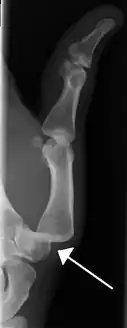

- Finger: Interphalangeal (IP) or metacarpophalangeal (MCP) joint dislocations[31]

Radiograph of left index finger dislocation